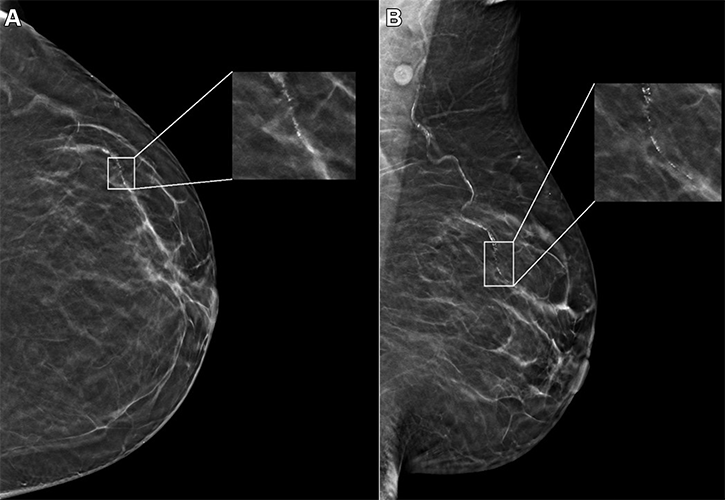

Example mammogram assigned a false-positive case score of 96 in a 59-year-old Black patient with scattered fibroglandular breast density. (A) Left craniocaudal and (B) mediolateral oblique views demonstrate vascular calcifications in the upper outer quadrant at middle depth (box) that were singularly identified by the artificial intelligence algorithm as a suspicious finding and assigned an individual lesion score of 90. This resulted in an overall case score assigned to the mammogram of 96.

https://doi.org/10.1148/radiol.232286 © RSNA 2024